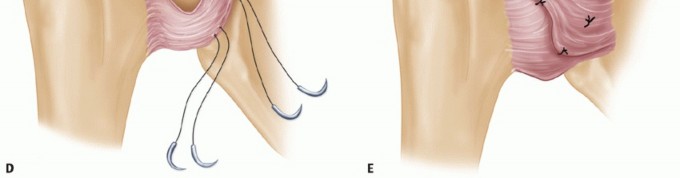

TECH FIG 3 • The anterior capsulolabral reconstruction procedure. A. The subscapularis is divided horizontally in line with its fibers at the junction of the upper two-thirds and lower one-third. B. A transverse capsulotomy is now made in the middle of the capsule extending medial to the glenoid rim. C. The capsule is elevated off the glenoid subperiosteally to allow for superior and inferior capsular advancement. (continued) A transverse capsulotomy is now made in the middle of the capsule extending medial to the glenoid rim. The capsule is elevated off the glenoid subperiosteally to allow for superior and inferior capsular advancement (TECH FIG 3C).

The laterally based inferior flap is then shifted superiorly and secured to the intra-articular portion of the glenoid rim using transosseous sutures to attempt to recreate the labral “bumper” (TECH FIG 3D,E).

The superior flap is then shifted medially and oversewn to the inferior flap.

Because the subscapularis tendon is not detached, active assistive rehabilitation exercises are begun immediately on postoperative day 1, and rehabilitation is progressed more rapidly.